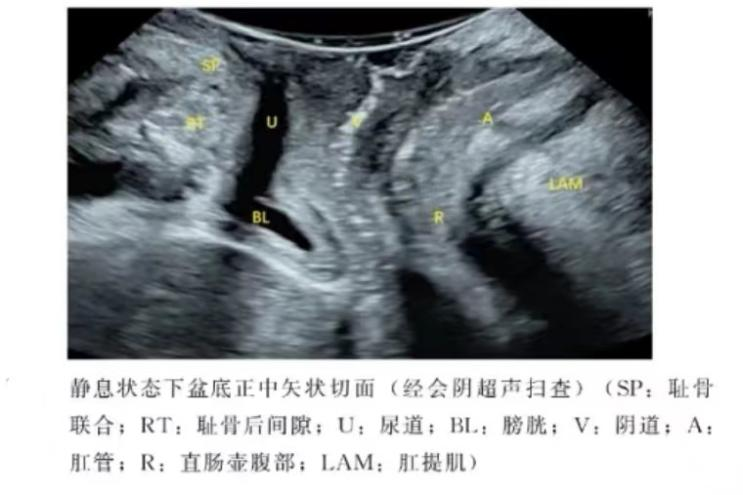

盆底超声是将探头放于会阴部或阴道内,通过指导患者正确的完成缩肛和Valsalva动作,动态观察盆腔脏器的位置变化,从而判断盆腔脏器的脱垂情况及盆底肌肉的完整性。

盆底三维成像技术还可以获得完整的肛提肌裂孔的立体声像图,准确测量裂孔大小,直观地观察肛提肌及韧带走形及损伤程度。盆底超声被广泛应用于盆底功能障碍性疾病的诊断和治疗后疗效的评估。